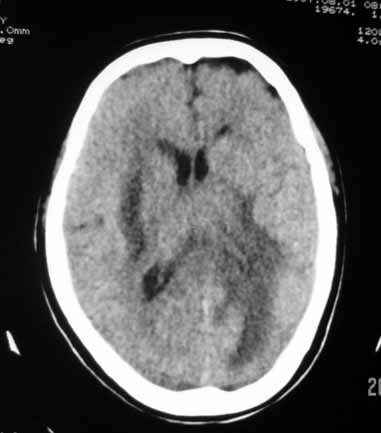

典型的“转移瘤”。

(多发 小病灶,大水肿!)

小病灶,在水肿。符合转移瘤改变。

小转移大水肿,支持转移

脑内多发结节性小病灶,周围水肿明显,结合结肠癌病史,典型的转移瘤。